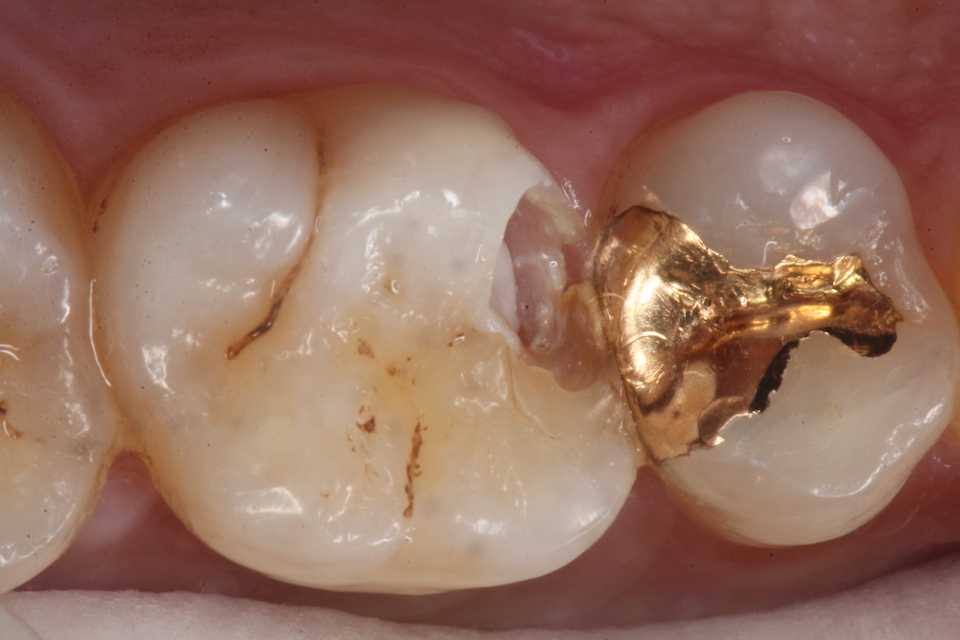

とりあえずα-TCPを除去し始めたが内部の象牙質は硬化している。虫歯はα-TCPで治る。

再度3MIX+α-TCPで覆罩してCR充填した。

歯肉縁下に虫歯やクラックが及んでいたができる限り取り除いた。歯肉側のエナメル質は取らざるを得なかったが、これ以上取ると大穴が開く寸前までいった。象牙質のクラックが少し見えるが、α-TCPで治って欲しい。

では時系列でどうぞ

こういった歯肉縁下の窩洞はストリップスを使うと出血するだけで上手くいかないだろう。ましてやラバーダムなど歯肉縁下にはかからない。